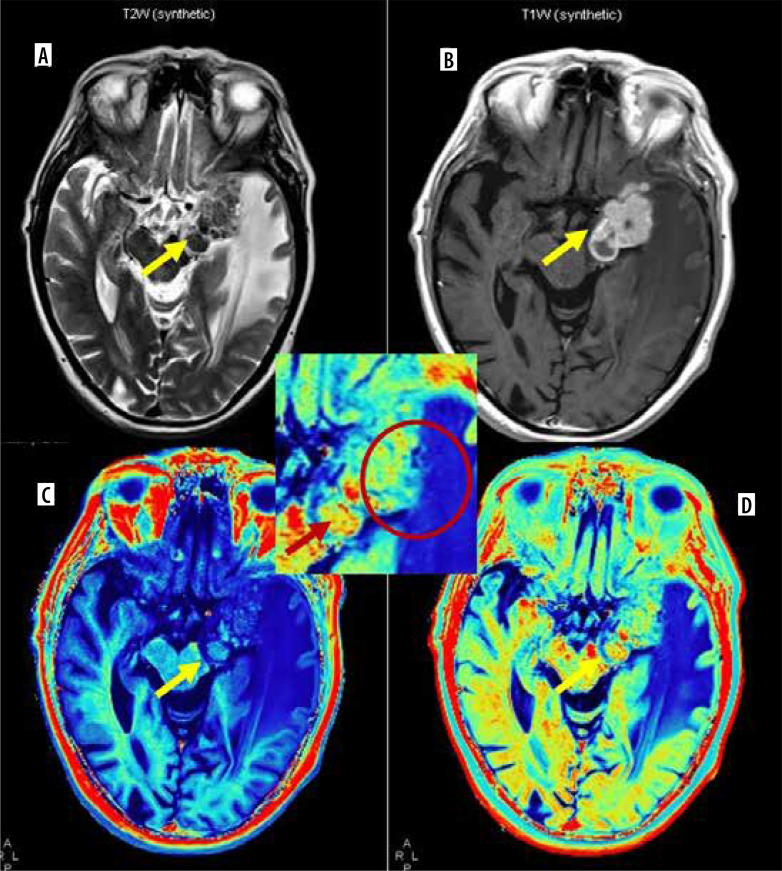

Purpose: Synthetic magnetic resonance imaging (MRI) allows reconstruction of multiple contrast-weighted images from a single acquisition of multiple delay multiple echo (MDME) sequence with quantitative relaxometry (longitudinal relaxation rate [R1], transverse relaxation rate [R2], and proton density [PD]) in a shorter acquisition time. We tried to explore synthetic MR-based relaxometry to differentiate central nervous system (CNS) tuberculomas from primary CNS neoplasm like glioblastoma.

Material and methods: Ten cases of CNS tuberculoma and 14 cases of glioblastoma underwent pre- and post-contrast synthetic MRI. R1, R2, and PD values were calculated from lesion core, wall, and perilesional oedema using free-hand region of interest and compared across the 2 groups.

Results: Both pre- and post-contrast R1 and R2 relaxation rates from core were significantly higher in tuberculoma (mean pre-contrast R1 - 0.93, R2 - 15.02; post-contrast R1 - 1.51, R2 - 15.48) from glioblastoma (mean pre-contrast R1 - 0.36, R2 - 4.58; post-contrast R1 - 0.43, R2 - 4.78). The same values were higher in perilesional oedema of glioblastoma (mean pre-contrast R1 - 0.75, R2 - 9.9; post-contrast R1 - 0.78, R2 - 10.48) compared to tuberculoma (mean pre-contrast R1 - 0.68, R2 - 8.57; post-contrast R1 - 0.72, R2 - 8.67). No significant difference was seen between relaxometry parameters from the walls of lesions.

Conclusions: Synthetic MR-based relaxometry can be useful in distinguishing CNS tuberculomas from glioblastoma. R1 and R2 relaxation rates from core of the lesions are most important in differentiating the two with R1 value > 0.852 and R2 value > 11.565 from core strongly suggests tuberculoma over glioblastoma.